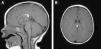

The patient was lost to follow-up but returned when she was 8 months old. A brain magnetic resonance imaging (MRI) study showed an interhemispheric hyperintense mass on both T1- and T2-weighted sequences and a hypointense mass on fat-suppressed T2-weighted images. These findings were consistent with a lipoma (1.8cmA-0.7cmA-0.6cm on the anteroposterior, longitudinal, and transverse planes, respectively) associated with hypoplasia of the splenium of the corpus callosum. No tracts or other forms of communications were observed between the cerebral and frontal lipomas.

The patient was referred to a pediatric neurosurgeon, who decided to keep her in clinical follow-up. A second MRI study was performed 6 months later and no changes were observed (Fig. 2). The patient was also referred to the otolaryngologist to rule out Pai syndrome; the results of nasal fibroscopy were within normal limits. A year after diagnosis, the patient is still in follow-up, with excellent developmental milestones and no evidence of neurological complications.